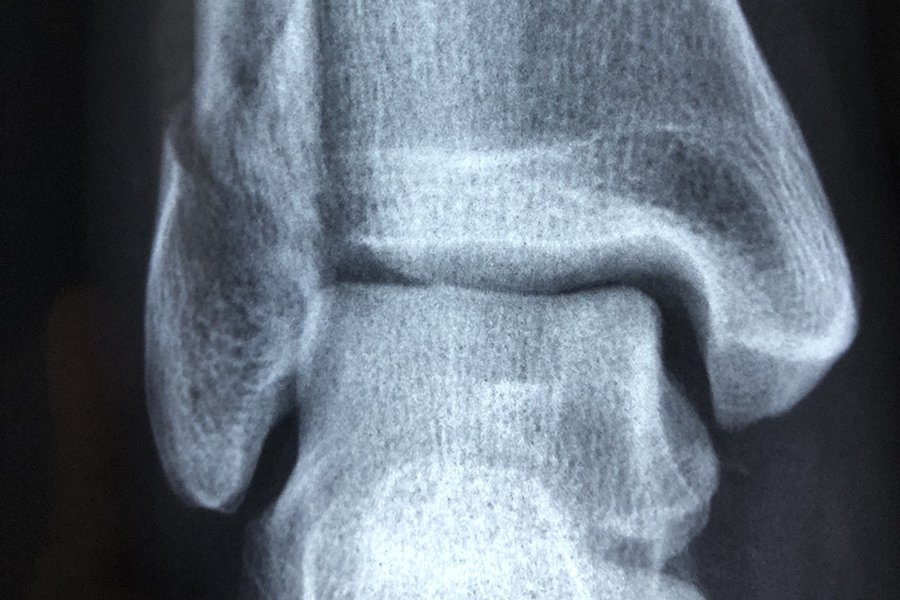

Команда, в которую вошли исследователи из ANU и больницы Канберры, собрала КТ-снимки у большой выборки здоровых людей и пациентов, ожидающих замены коленного сустава.

Используя передовые методы анализа изображений для создания 3D-моделей сотен костей коленной чашечки, команда затем применила методы моделирования формы для визуализации и измерения формы поверхностей коленной чашечки в трех измерениях.

Хотя они не нашли уникальных особенностей среди коленных чашечек женщин по сравнению с мужчинами, они обнаружили изменения в поверхностях коленной чашечки, которые были более выражены у людей с остеоартритом.